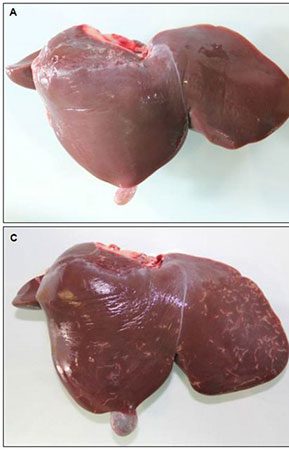

- Surgery and biopsy

- Create and induce a variety of animal models